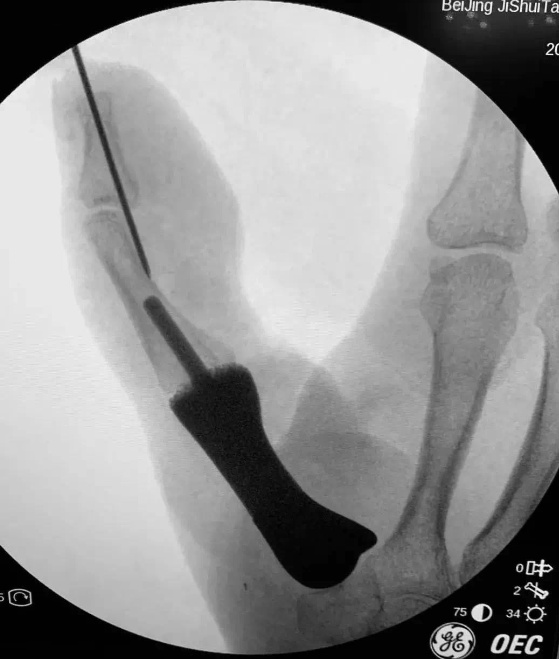

陈山林团队术前详细规划,反复推演手术流程。3月5日,在陈山林等专家共同协作下,顺利完成了假体置入,腕掌关节韧带重建等复杂精细手术。手术过程非常顺利,术中影像显示,假体位置得当,腕掌关节稳定且具备一定的活动度;再造拇指外观满意,长度合适,各皮瓣存活良好;足部供区外观良好。